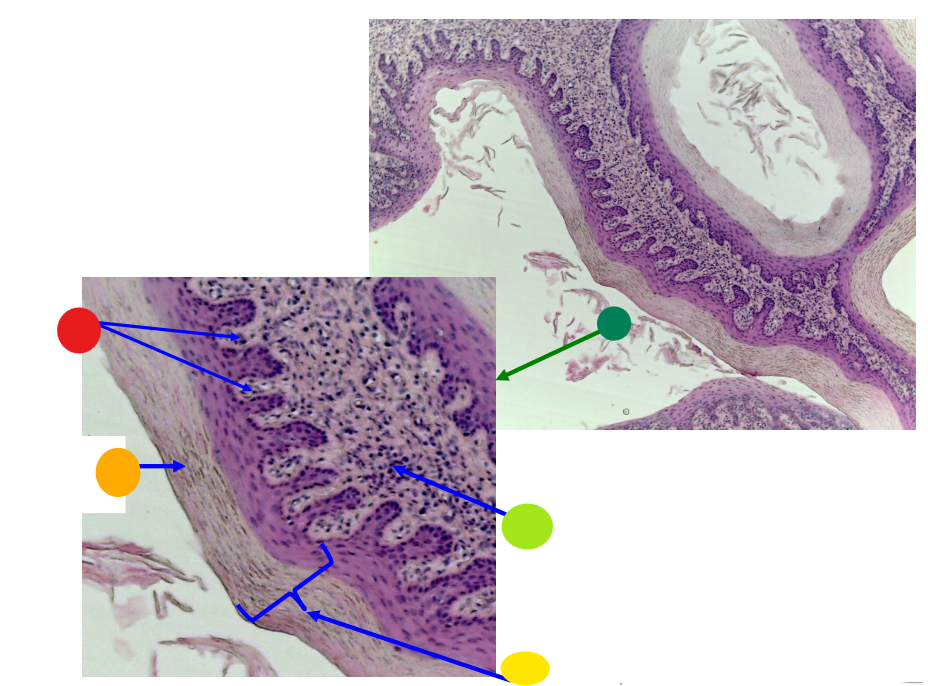

red

tunica albuginea

orange

primordial follicles

yellow

follicular cells

light green

primary oocyte

dark green

granulosa cells

light blue

primary follicles

what is this?

ovary

red

primordial follicles

red

primary follicles

red

tunica albuginea

orange

primary oocyte

yellow

primordial follicles

red

granulosa cells

orange

primary oocyte

what is this

primary follicle

red

tunica albuginea

orange

primordial follicles

red

primary follicle

orange

secondary follicles

what is this

tertiary follicle